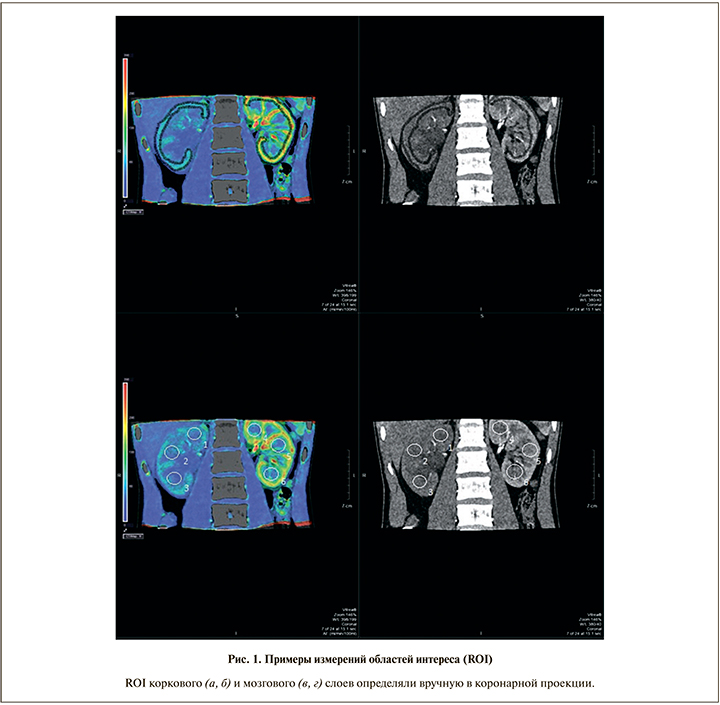

Обработку полученных данных для получения кривой плотности/времени осуществляли на рабочей станции Vitrea при помощи протокола 4D Single Imput Perfusion, в процессе которого измеряется плотность ткани в двух различных областях исследования – ROI (region of interest): в афферентной артерии (брюшной аорте) и интересующей ткани (корковый и мозговой слои почки). Оценку перфузии ткани осуществляли с помощью метода одиночной наклонной кривой (рис. 1). Суть данного метода в том, что контрастное вещество при внутривенном введении распределяется только в одном объеме (например, в пространстве внутри сосудистого русла). Данный фактор позволяет рассчитывать скорость кровотока – AF (arterial flow), которая определяется как скорость прохождения определенного объема крови через заданный объем ткани за единицу времени и имеет размерность мл/100 г/мин (рис. 2, 3). Также при анализе данных применяли метод Патлака [17–22], в основу которого положено динамическое распределение контрастного вещества между двумя объемами: внутрисосудистым и внесосудистым. Данный метод позволяет рассчитывать эквивалентный объем кровенаполнения – BV (blood volume), определяемый как общий объем крови, проходящий через сосуды выбранного участка ткани и имеющий размерность мл/100 г.